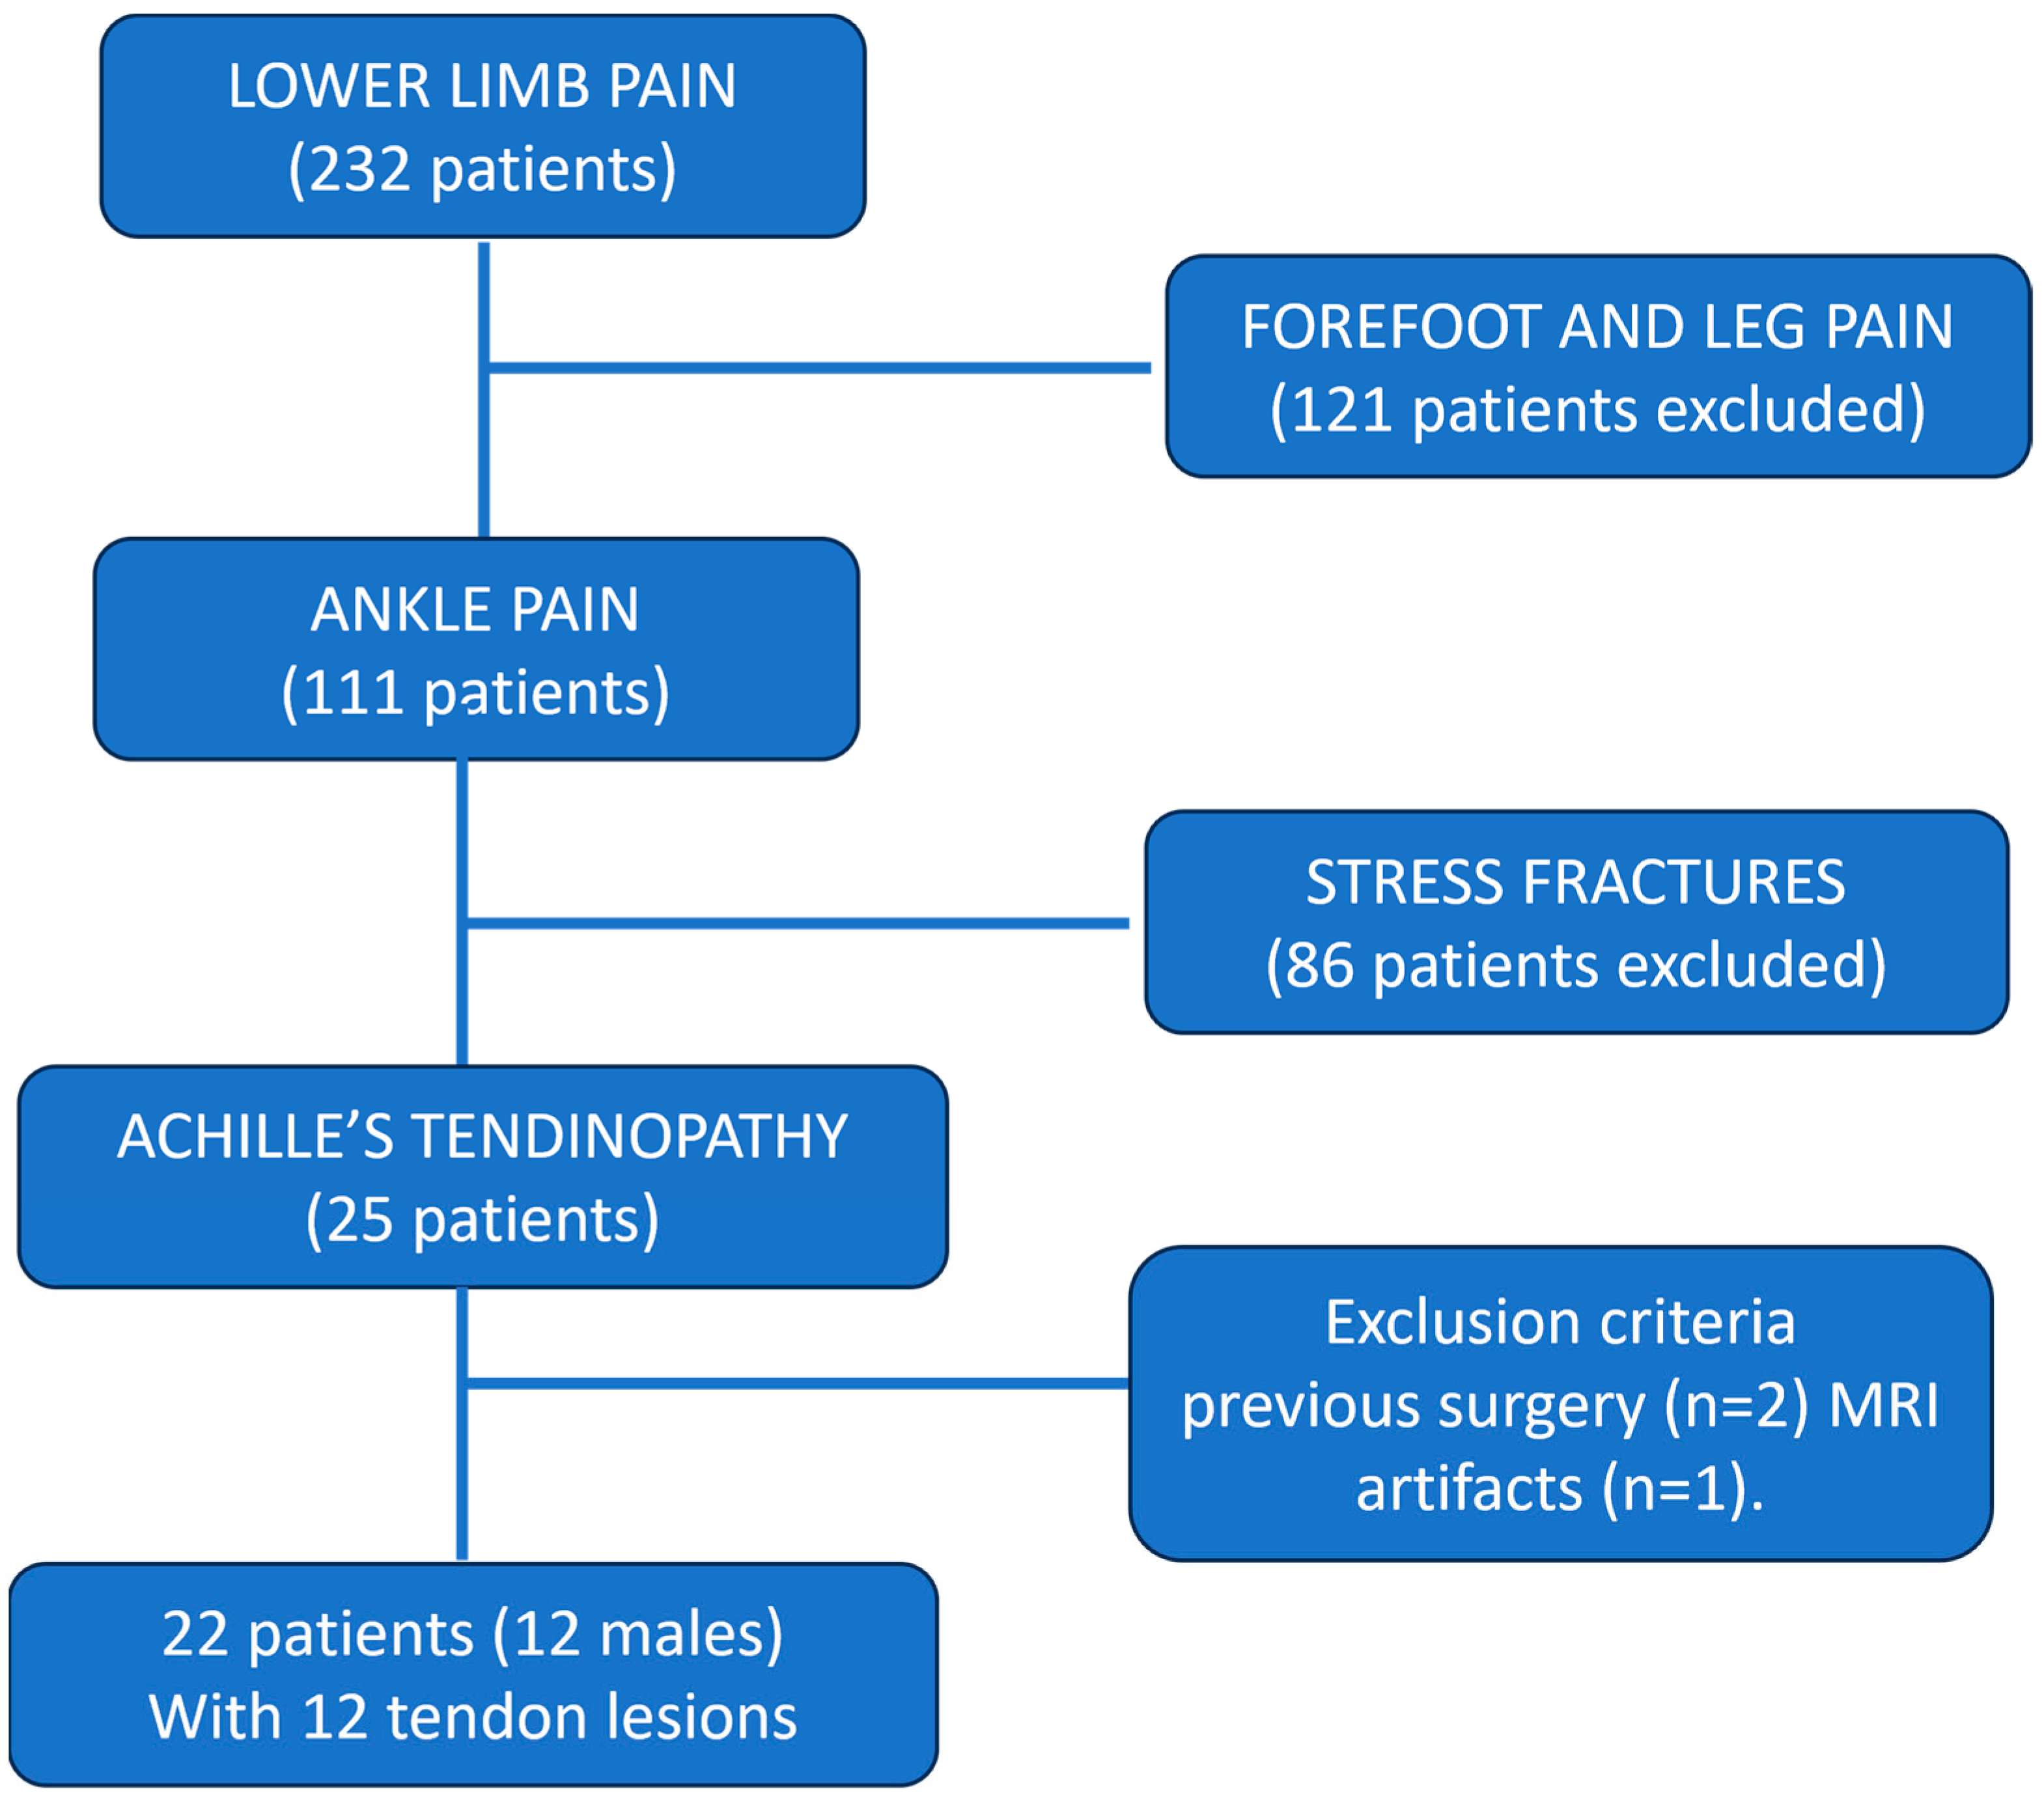

2.1. Participants

3.1. Patients Results